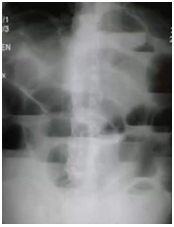

【臨床判讀】根據(jù)下面X線片判斷臨床意義。(5分)

單純性小腸梗阻。

單純性小腸梗阻是小腸內(nèi)容物運(yùn)行障礙所致的急腹癥。典型臨床表現(xiàn)為腹痛、腹脹、嘔吐。腹部立位片顯示腹腔內(nèi)多發(fā)階梯狀氣液平面。